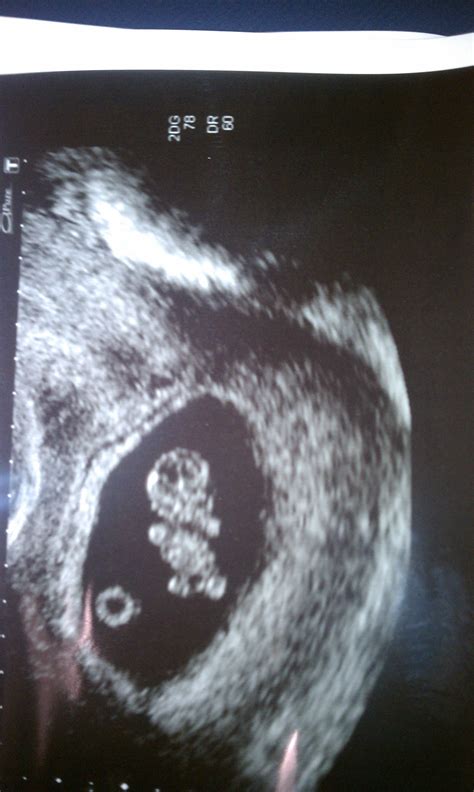

What Can Be Seen During a 9 Weeks Ultrasound?

At 9 weeks, the fetus is still very small, but several key features can be visualized:

• Gestational Sac: This is the fluid-filled structure that contains the embryo.

• Yolk Sac: This structure provides early nutrition to the embryo.

• Embryo: The embryo itself, which is about the size of a grape, can be seen with a distinct head and body.

• Fetal Heartbeat: The heartbeat is usually visible and audible, providing reassurance of the fetus’s health.

• Amniotic Fluid: The fluid surrounding the embryo, which protects and cushions the developing fetus.

📝 Note: The clarity of the images can vary based on factors such as the position of the uterus, the amount of amniotic fluid, and the skill of the technician.